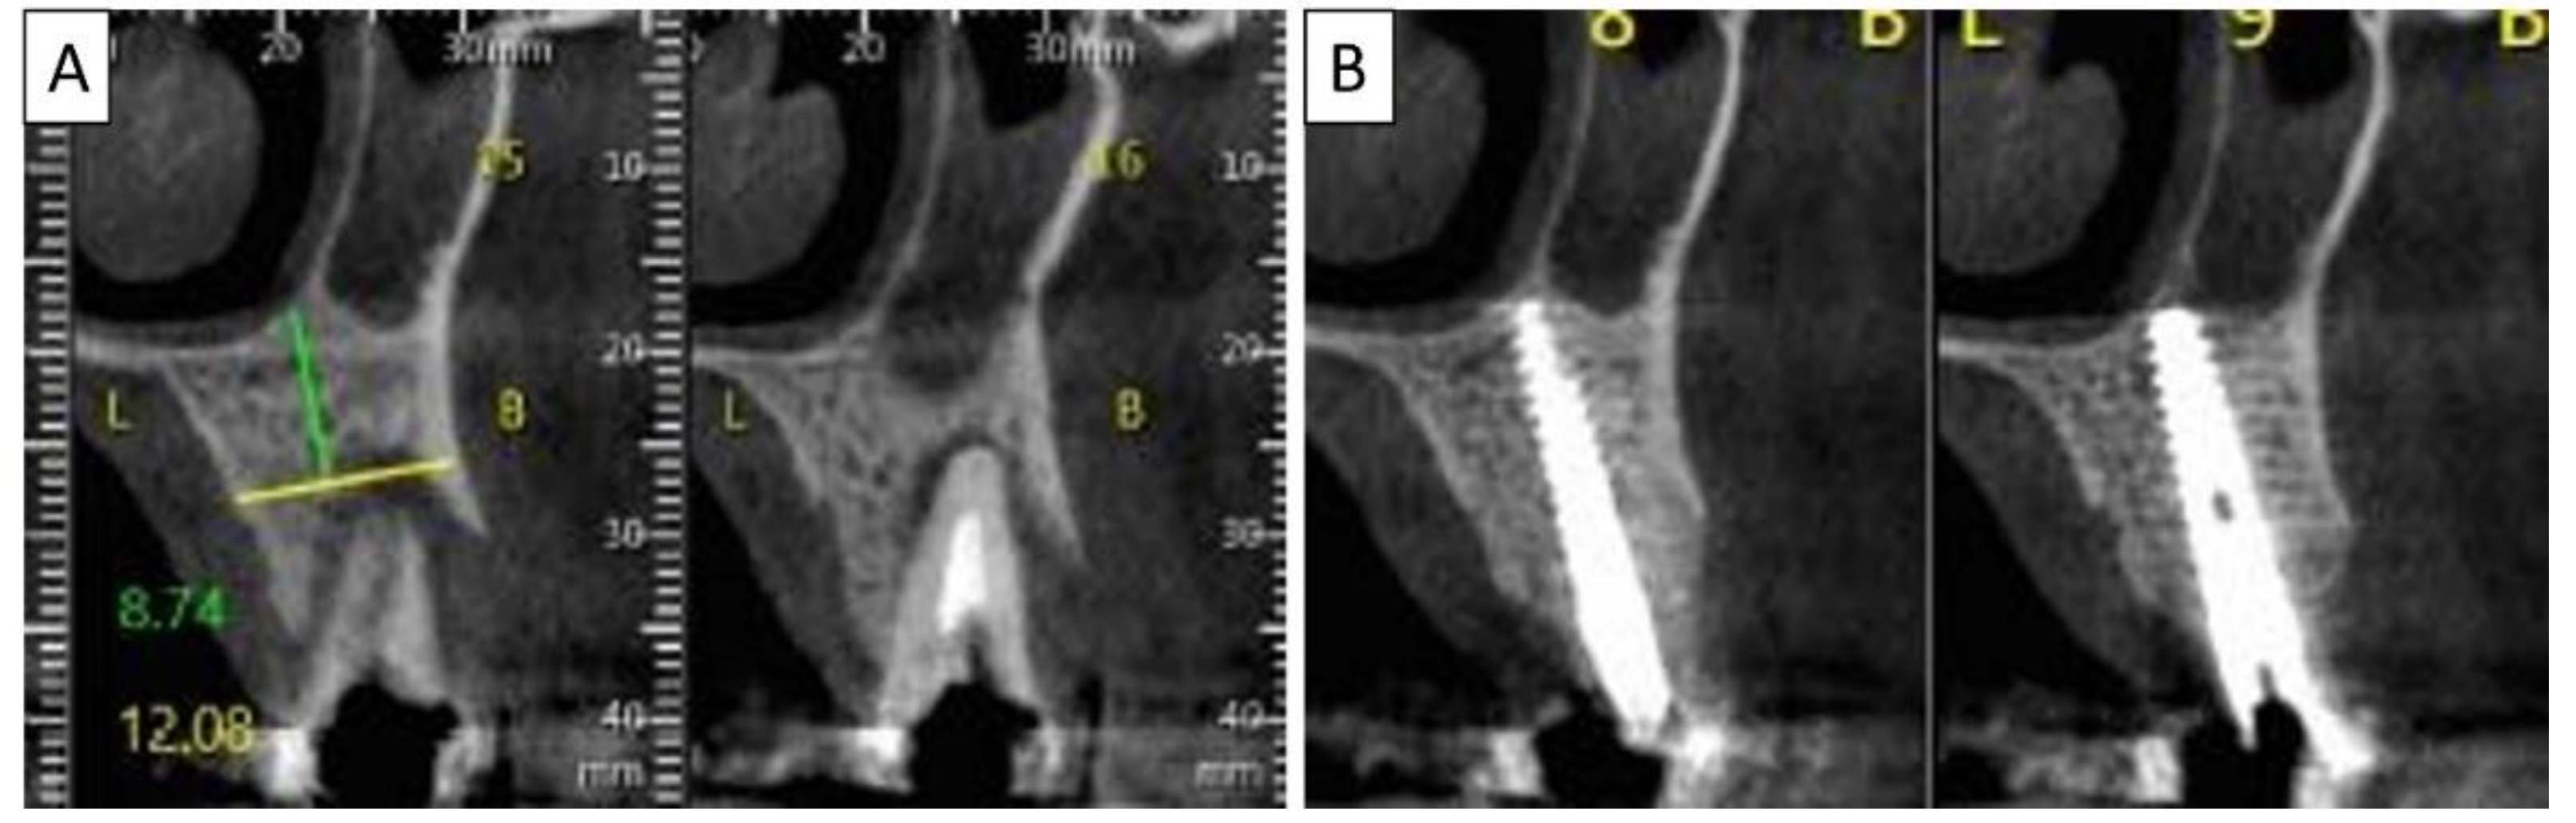

Figure 5.

(A) Coronal CBCT section shows tooth 25 with vertical root fracture and destroyed buccal bony wall and intact palatine. (B) The coronal CBCT section shows the placed implant in the region of tooth 25 and the complete regeneration of the cortical wall.